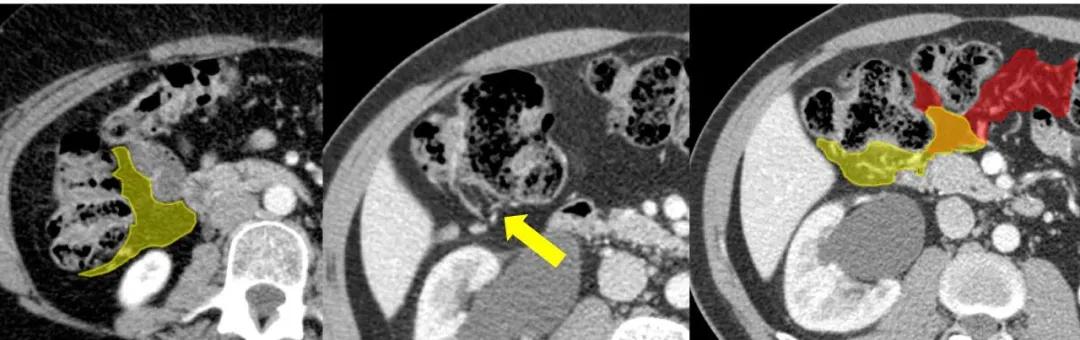

右侧结肠系膜(黄色)和横结肠系膜(红色)间的汇合。

横结肠系膜(红色)和横结肠动脉(箭头)。